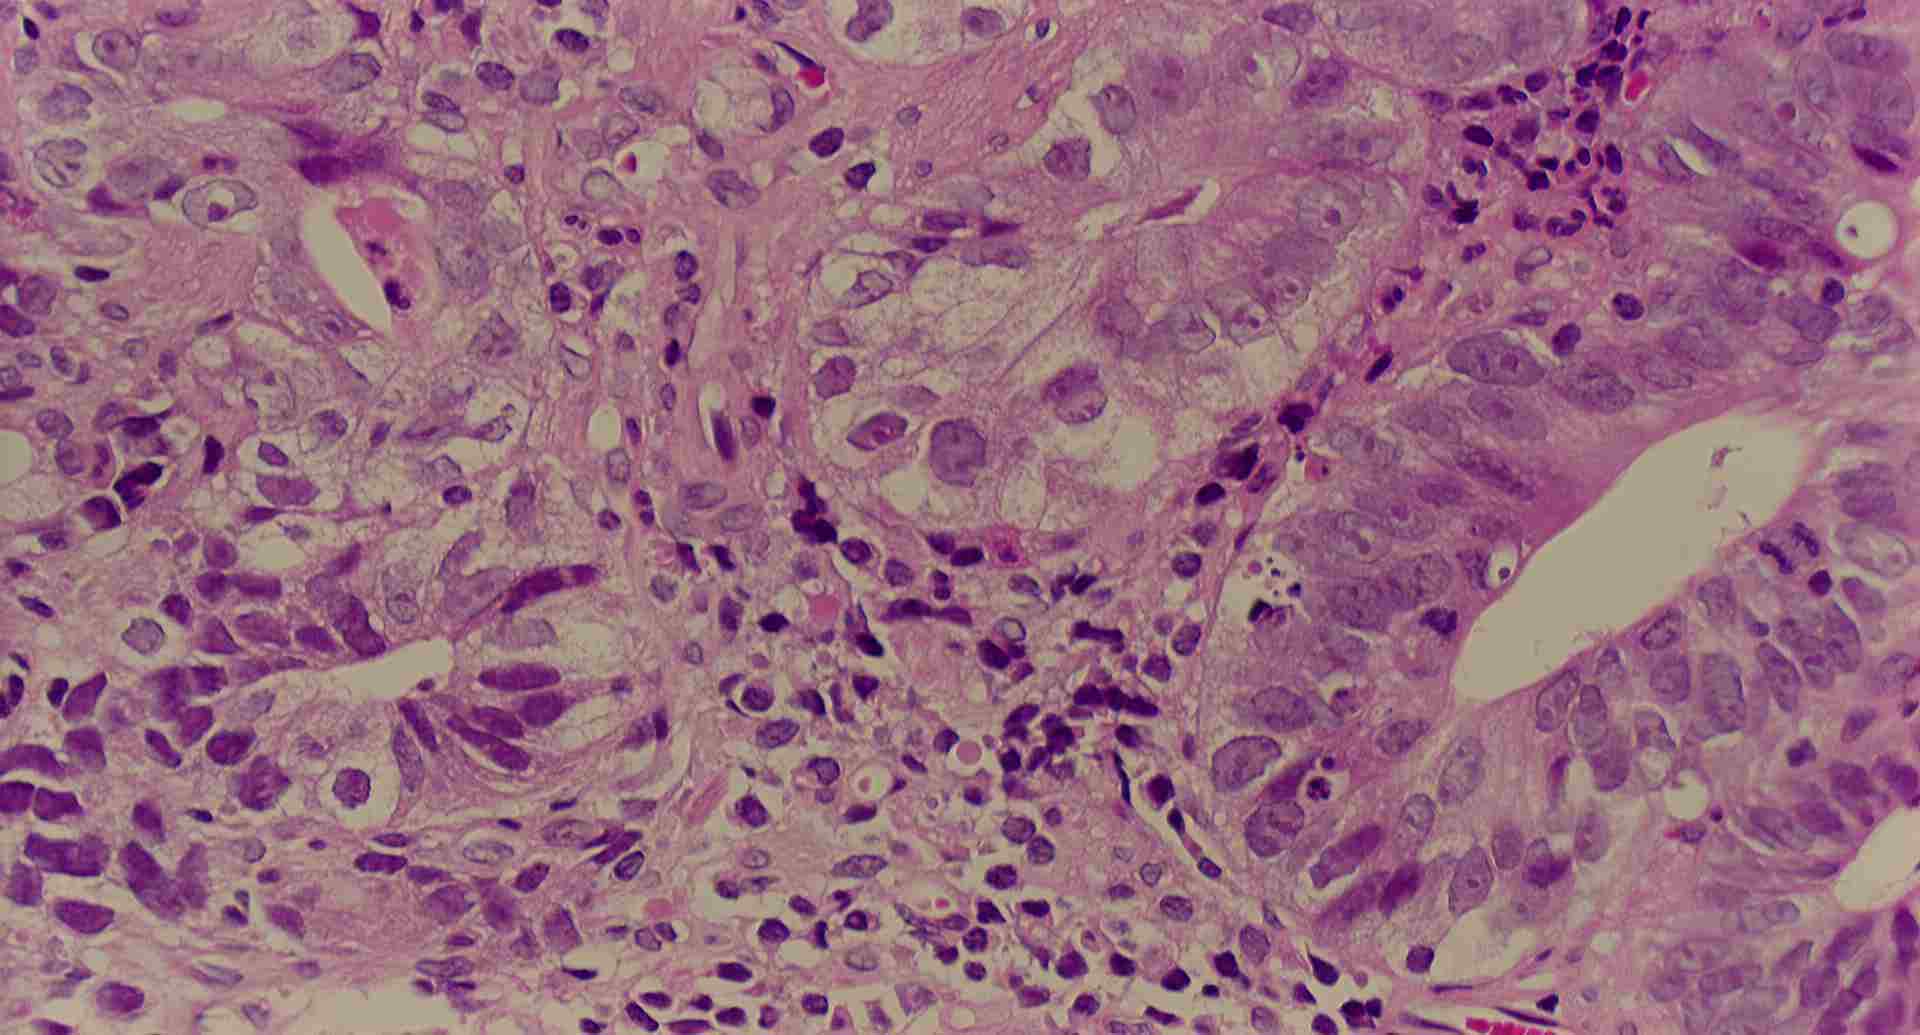

標本9